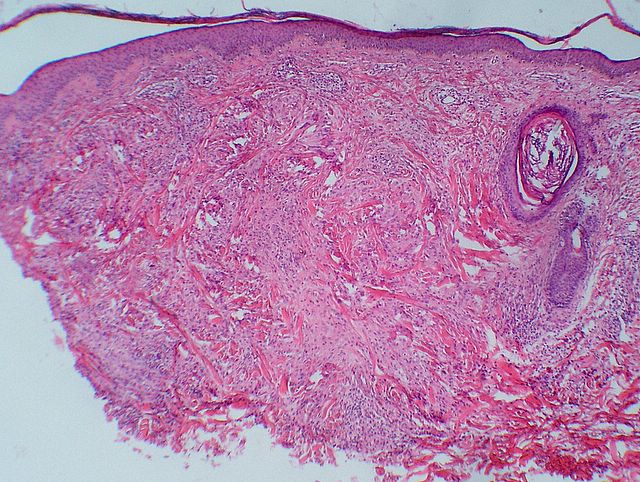

Descripcion histologica

Diagnostico